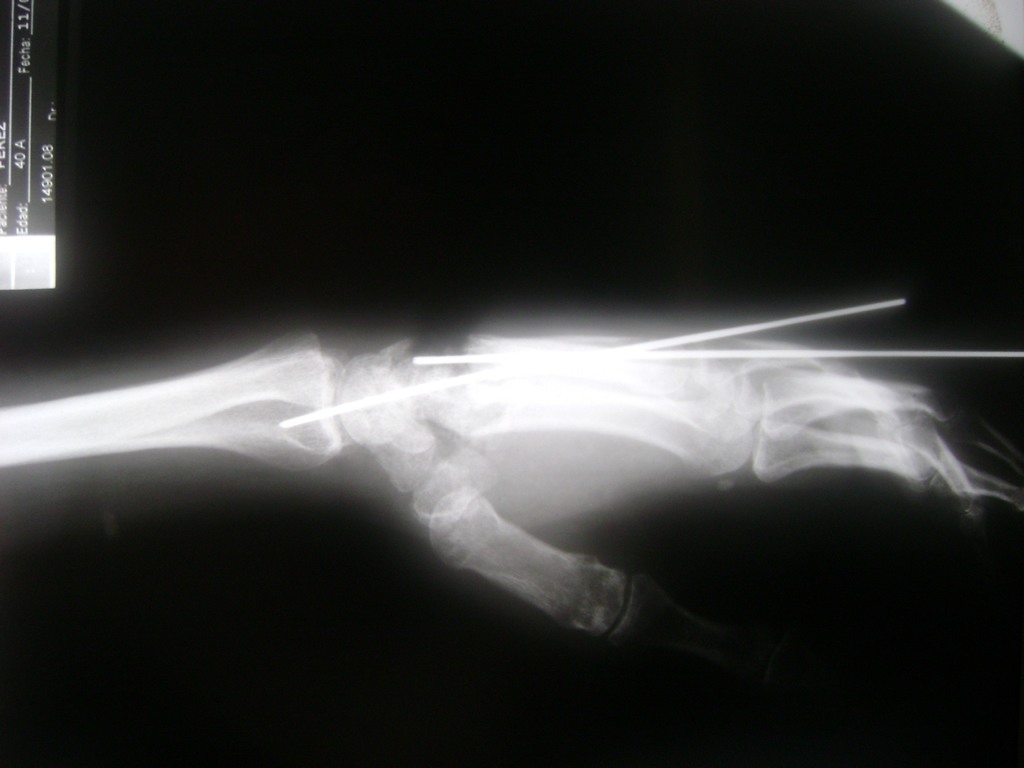

Cirugías de Muñecas

Los procedimientos más comunes en cirugía de la mano son aquellos destinados a reparar traumatismos, incluyendo lesiones de tendones, nervios, vasos sanguíneos, y articulaciones; huesos fracturados; y quemaduras, cortes, y otros daños de la piel.